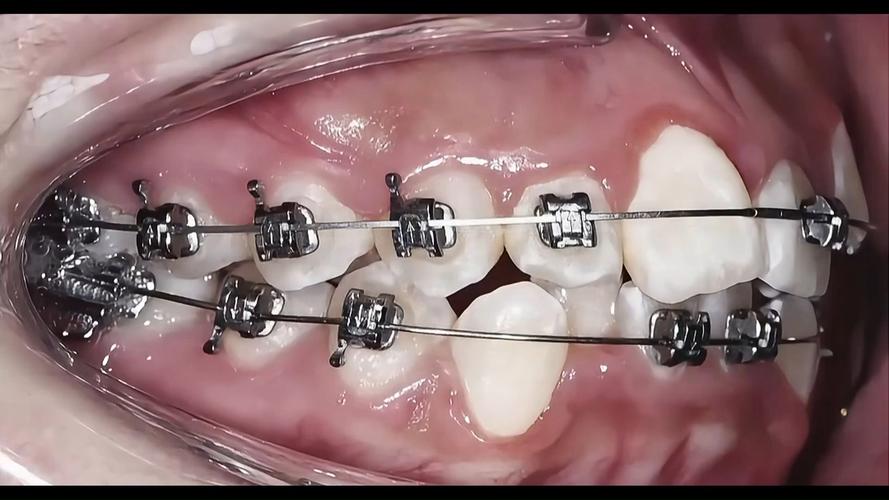

在正畸治疗中,“大牙垫起来”是临床上常见的调整咬合关系的手段,通常指通过在上下颌后牙(磨牙)区域放置特定材料的垫高装置,暂时改变咬合接触点,为后续的牙齿移动或咬合功能调整创造条件,这一操作看似简单,实则涉及咬合力学、牙齿移动规律及颌面功能协调等多方面考量,是正畸医生精细调控治疗进程的重要技术之一。

正畸治疗的本质是通过外力引导牙齿在牙槽骨中移动,最终达到排列整齐、咬合稳定的目标,但牙齿移动并非孤立过程,咬合关系(上下牙齿的接触方式)直接影响移动方向、效率及最终稳定性,大牙(磨牙)作为口腔中体积最大、承担主要咀嚼功能的牙齿,其咬合状态对整个颌系统的平衡至关重要,当存在咬合干扰、咬合平面异常或需要特定牙齿移动方向时,垫高大牙可暂时调整咬合接触,主要作用包括:

“垫大牙”的常用类型与材料选择

根据治疗目的和作用部位,正畸医生会选择不同类型的垫高装置,材料需具备生物相容性、耐磨性和可调适性,以下是常见类型及特点: